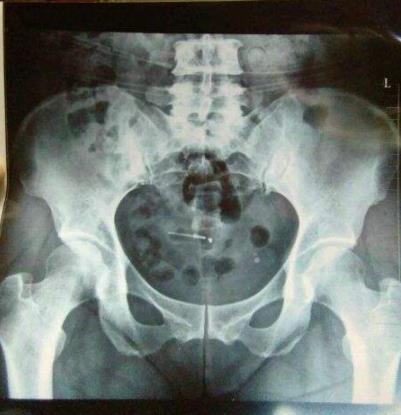

第一步:取环术前检查:

1、术前检查血常规,白带常规,b超检查。

2、术前禁食水4小时。

3、已绝经的妇女,如子宫已萎缩,术前需服用一周补佳乐或倍美力。

4、对宫口紧的患者,术前服用米索0.6mg,2小时后再手术。